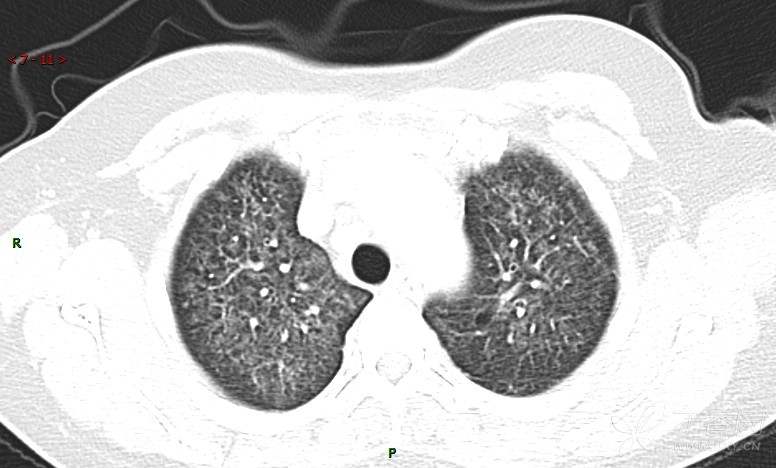

肺内弥漫性网状结节影,PET-CT却无阳性病灶,这是?(附其他2例链接)

女性,58岁,阵发性咳嗽2月,加重1月。

患者于2月前无明显诱因出现咳嗽,以阵发性干咳为主,接触冷空气后咳嗽明显,偶咳少量白色泡沫样痰,咳嗽剧烈时感憋喘,无发热、盗汗,无头痛、头晕,无胸痛、咯血,无恶心、呕吐,无腹痛、腹泻,无尿频、尿痛等不适,于当地医院给予肌注及静脉药物治疗,具体药物名称不详,效果欠佳,近1月来患者咳嗽频率较前增加,咳嗽剧烈时感双侧季肋区疼痛不适,10余天前出现发热,体温在38℃左右,伴畏寒、寒战,无头痛、头晕,无纳差、乏力等不适,药物治疗后体温降至正常,仍阵发性咳嗽,今为求进一步诊治,就诊于我院急诊,因呼吸内科暂无床位,急诊门诊以“肺间质病变”收入急诊留观室,给予“抗感染、止咳”等对症支持治疗后,今日以“肺间质性病变”收入我科,患者自本次发病以来,神志清,精神可,饮食尚可,睡眠一般,大小便正常,体重较前无明显变化。

患者活检肺组织后行PET/CT检查